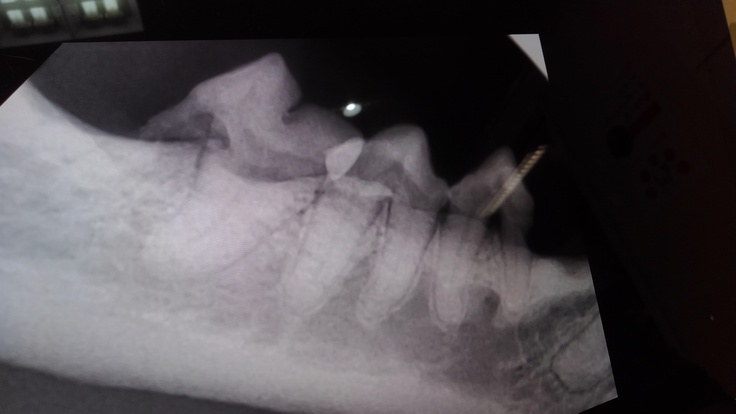

手術前に撮ったレントゲンです。

少しわかりづらいですが、重度の歯肉炎により歯茎が下がり歯の根っこが浮いた状態になっています。

結局犬歯以外の歯は全て抜くことになりました。